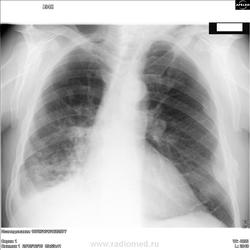

В первом случае подумал бы на мтс, от второго туберкулезом пахнет.

Не буду томить:первому поставил центральный рак справа и мтс, второму-диссеменированный туберкулёз в фазе распада.На следующей неделе сверка с онкологом и ПТД.

2. Возможен и тбц. Посевы , лечение, наблюдение. Не снимал бы версию полостной формы с мтс.

Да-а,красивые!Вы правы,у второго точно туберкулез,только не диссеминированный,а инфильтративный,в фазе распада и обсеменения.А с первым надо поработать-там много чего!

С первым согласен. Со вторым тоже, но написал бы инфильтративный туберкулёз в фазе распада и диссеминации

Второй случай, на мой взгляд, весьма затруднителен, по всей видимости, "собака" зарыта в обычном анализе мокроты.

Весьма трудно определиться по поводу "формы туберкулёза", и это довольно странно, если таковой имеется (туберкулёз). Да, и толстостенный "каверкот" слева довольно банально нагловато себя ведет, как бы говорит, что мол вот "Я", она, мол "каверна"...Я...

Да и каверна ли это?Весьма наглая полость.Может ведь и стафилококк кренделя выписывать,и нам нос утереть.Вопрос к автору ветки-а эти двое не алкоголики,тунеядцы,пьяницы?И возраст каков?

больше тянет на каверну ,так по периферии видны ацино-нодулярные очаги +уплотнение по типу инфильтрации  справа .что касается формы тбц описал бы как кавернозный тбц с лимфогенным заносом в правую верхнюю долю

Это не кавернозный туберкулез.

Мнение по второму случаю: двусторонняя деструктивная пневмония - на первое место; туберкулез и онко - на второе.

У второго пациента -инфильтративный туберкулез в/доли в фазе распада и обсеменения

можно предварительно рассматривать как двухсторонний инфильтративный туберкулез легких в фазе распада. Жаль нет левой боковой рентгенограммы.

Когда говорила,что это не кавернозный,я имела в виду формы туберкулеза(т.е. картина ближе к инфильтративному,чем к кавернозному туберкулезу).

Кольцо предполагаемой каверны (тень стенок полости каверны) не замыкается. Каверна имеет более четкий внутренний контур. Здесь не дотягивает немного до каверны, хотя визуально очень похоже. Плюс инфильтративные изменения в правом легком. Форма инфильтративная.

По второму пациенту спешу сообщить о выявлении КУМ+ в ПТД,о форме туберкулёза фтизиатры ещё сами не определились.С онкологом ещё не сверялся.

Спасибо,Сергей,что сообщили.Сомнений не было.А форму фтизиатры,действительно ,"рожают" с трудом(тут есть нюансы,да и долго объяснять).У нас-верят рентгенологам.Осталось дождаться результатов от второго "красавчика "-проблемный.Надеюсь,Вы будете в курсе и сообщите.